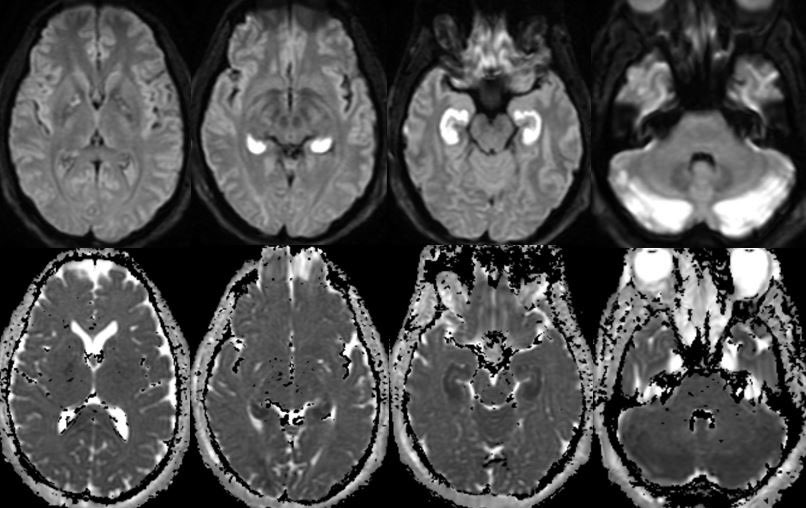

▶️CHANTER syndrome is likely a diagnosis on the spectrum of opioid induced amnestic syndrome (which is isolated to the hippocampus) and pediatric opioid use-associated neurotoxicity w/ cerebellar edema (POUNCE)

English